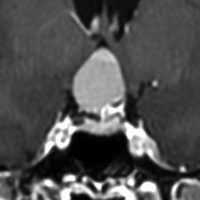

8歳で両側の視力低下が生じました。眼科では精神的なものと診断されて,4ヶ月くらいで右視力 0.4(耳側半盲),左指数弁となりました。のう胞性頭蓋咽頭腫で大きな骨化を伴うもので1月くらいの間に全盲になるかもと判断しました(失明寸前です)。

矢印の先に見えるように下垂体は正常の形態です。この画像から灰白隆起の左後方,乳頭体の前方が腫瘍発生母地ということがわかります。尿崩症もなく下垂体機能は正常です。経鼻的な内視鏡手術で腫瘍の大部分を摘出すれば下垂体機能は廃絶します。

とにかく失明を避けるために急いで経蝶形骨洞手術(transsphenoidal-transtuberculum sellae approach)で腫瘍のう胞の減圧をしました(緑の矢印の経路 by 函館中央病院加藤功先生)。その後に前頭開頭で腫瘍を全摘出しました(右側の画像)。尿崩症はでましたが下垂体前葉機能は正常です。

右視力 0.45,左明暗弁の視力が残りました。でももし,経鼻手術をしないでいきなり開頭すればおそらく全盲になっていた例です。